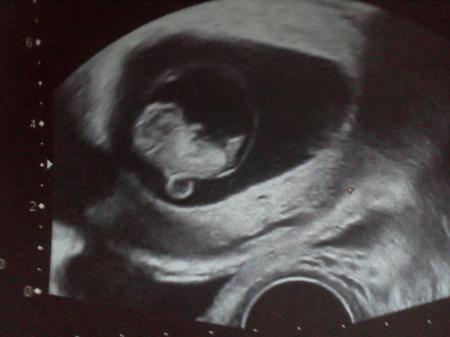

es ist geschafft! der arzttermin verlief super und ich durfte sogar 2 Bilder mitnehmen! :-) Das Kleine ist 2,4 cm groß und Arzt meinte, es ist alles wie es sein soll... Das Herzchen hat wie wild geschlagen und das war so schön zu hören, bin immer noch hin und weg. Mir stiegen gleich die Tränen in die Augen... Am 19.3. habe ich den nächsten Termin mit NFM.

bin 9+2, hatte ich mir auch ausgerechnet... Arzt sagt, das Kleine ist bestens entwickelt für 9+2...

Süß das Bild von deinem Würmchen.... Auf meinem Bild waren wir genau bei 9+2, die Ärztin hatte den Termin etwas zurück gesetzt, weil es ein bissl kleiner war. Aber beim Ultraschall am 17.2. sagte sie von der Größe wäre es jetzt bei 11+2 anstatt bei 10+6. Also gut entwickelt :-)

Bild zu